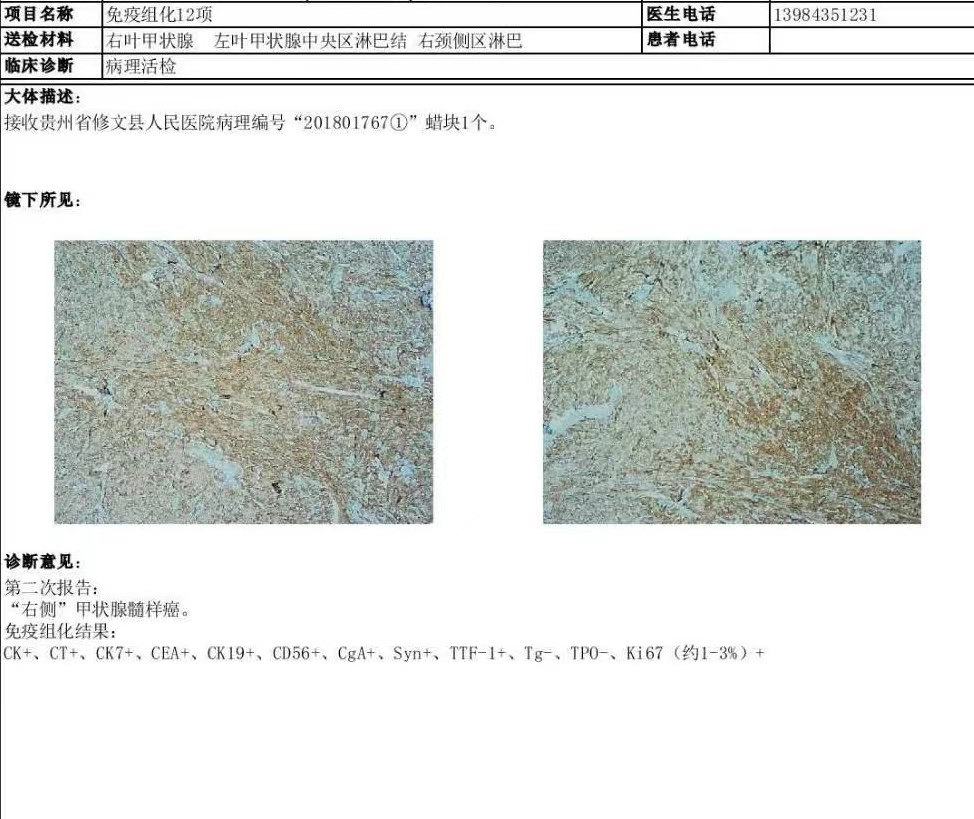

病理学方面,MTC显示滤泡旁C细胞分化的甲状腺恶性肿瘤,显微镜下见圆形或多角形细胞无粘附性生长,呈小梁状、器官样、巢状、腺样或假乳头状结构排列,肿瘤细胞染色呈细颗粒状,常被不等量的纤维血管间质分隔,部分间质见淀粉样物质沉积;免疫组化肿瘤细胞除表达CgA、Syn、CEA外,还表达C细胞特异度产物降钙素,但甲状腺球蛋白通常阴性,而TTEI、PAX8可局灶阳性,在瘤巢周边可见到S-100蛋白阳性的支持细胞。